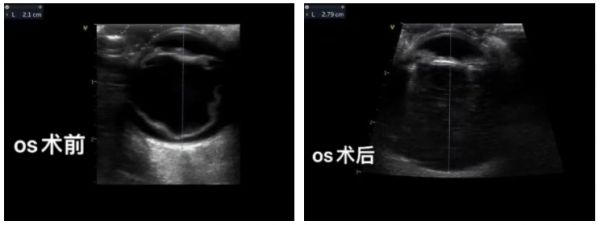

检查左眼威胁反应阴性,炫目阴性,瞳孔光反射阴性,泪液量左眼15,荧光阴性,眼压12,眼超见视网膜脱离。

经过全面的身体检查,结合患宠体况及相应检查结果,汪院长决定为患宠实施视网膜手术。这是一项相对复杂且需要专业医疗团队进行的眼科高阶手术,操作难度大、设备要求高,且术后护理要仔细。

在团队的共同努力下,手术最终顺利完成,患犬在术后一周恢复视力。后期需要定期为宠物进行复查,以确保视网膜成功复位并正在愈合。